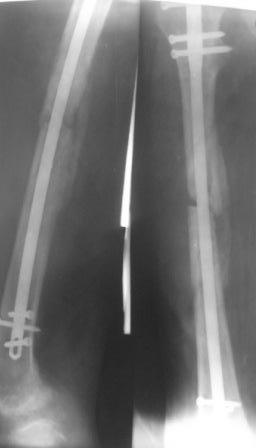

Остеомиелит после БИОС

Больной явился 13.03.10г. (около100 дней п/о ) с двумя свищами на бедре: один на уровне с/з бедра снаружи с гнойным отделяемым, второй на уровне дистального метафиза бедра тоже снаружи со скудным отд. Бедро не отечно, с признаками хрон. остеомиелита без обострений, ходит с двумя костылями с частичной нагрузкой на лев.ногу, до сих пор лечился у хирурга по м/жительства.

Уважаемые коллеги, может быть лучше использовать спейсер с антибиотиками (но у нас нет костного цемента), или другие варианты лечения? Р-снимок прилагается.